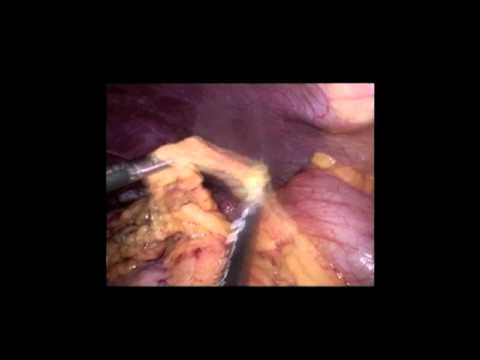

Réparation Laparoscopique Totale Extrapéritonéale...

Réparation totale extrapéritonéale bilatérale d'une hernie inguinale par laparoscopie à incision unique robot-assistée. Présenté par Luca Giordani.